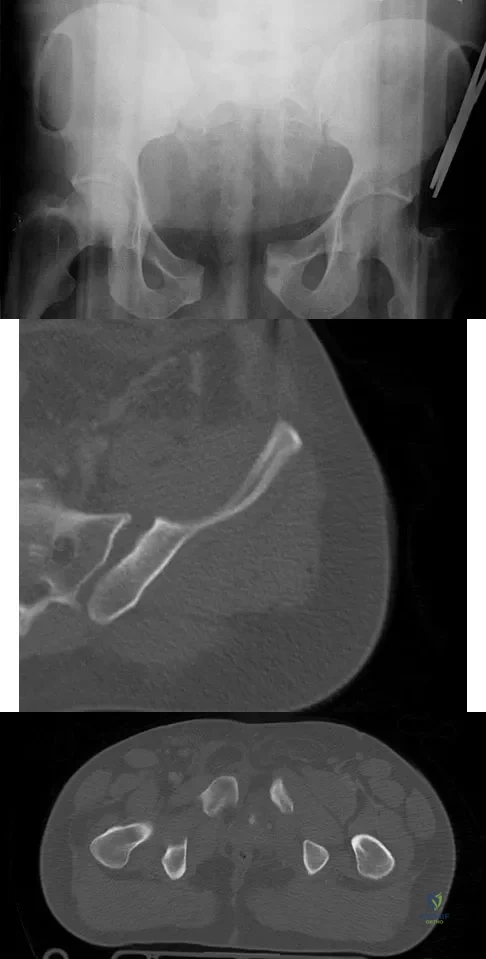

Question 79High Yield

A 22-year-old cheerleader who fell from the top of a pyramid now reports anterior and posterior pelvic pain. A radiograph and CT scans are shown in Figures 43a through 43c. What is the best treatment for this injury?

Explanation

Question 80